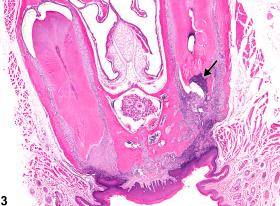

<p>Tooth - Inflammation, Chronic active in a male B6C3F1 mouse from a chronic study. Chronic active inflammation of the tooth is present (arrow).</p>

Tooth - Inflammation, Chronic active in a male B6C3F1 mouse from a chronic study. Chronic active inflammation of the tooth is present (arrow).